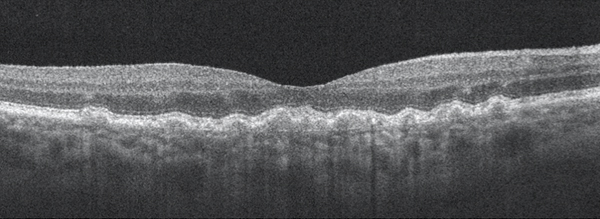

Before any imaging is employed, it is key to view the fundus via slit-lamp biomicroscopy and determine the presence and degree of macular pigment changes and the approximate size and number of drusen. Small drusen (<63 µm) are consistent with normal aging processes and present little increased risk of late AMD developing. Medium-sized drusen (63-125 µm) are more likely to progress to early AMD and signal an increased risk of developing late AMD; the presence of abnormalities in the retinal pigment epithelium (RPE) increases that risk (Figure 1).2

Figure 1. Dry AMD with disruption to the RPE layer with no evidence of subretinal fluid or choroidal neovascular membrane.